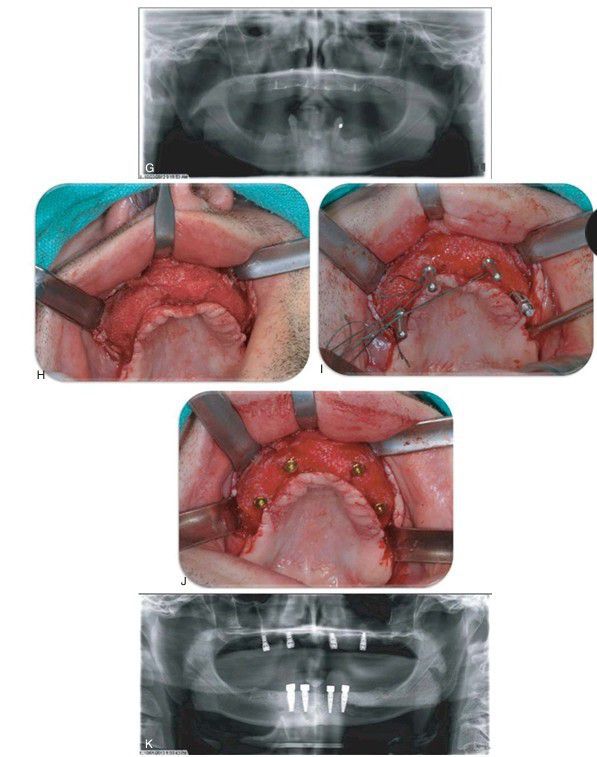

G) Postoperative Panorex of maxillary augmentation. (H) Surgical reentry 9 months after the grafting procedure. (I) Four direction indicators during implant placement at the time of titanium mesh removal. (J) Four implants placed into the regenerated bone with cover screws in place. (K) Postimplant placement Panorex.